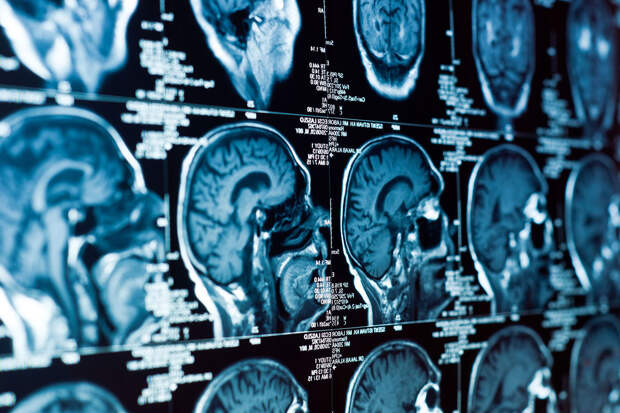

Ученые проанализировали данные сканирования мозга почти девяти тысяч детей и подростков.

Примерно у половины испытуемых было диагностировано психическое расстройство. Все четыре расстройства были связаны с аналогичными изменениями: уменьшением площади поверхности в ключевых областях, участвующих в эмоциональной регуляции и телесной осознанности. К ним относятся островковая доля мозга, энторинальная кора, средняя височная извилина и миндалевидное тело."Психические расстройства, начинающиеся в детстве, часто остаются недиагностированными или нелеченными на протяжении многих лет. Это ложится тяжелым бременем на людей, семьи и общество, приводя к потере человеческого потенциала", — отметила Софи Тауненд, ведущий автор работы и научный сотрудник факультета психологии Университета Бата.